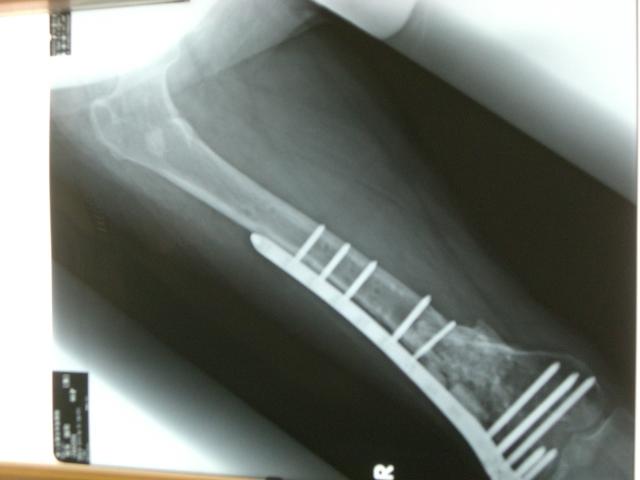

6/22¤Ë·è¹Ô¤¹¤ë»ö¤òDr¤ÈÂǹ礻¤·¤Æ¤­¤Þ¤·¤¿¡£

100415¤Î¹ü (1)¤Þ¤À¼ê½Ñ¤ÎÆâÍÆ¤ÇǺ¤ó¤Ç¤¤¤ë¤Î¤Ç¤¹¤¬

¤Þ¤º¡¢±¦É¨¤ò¶Ê¤²¤ë°Ù¤Ë

¶ÚÆù¤Ê¤É¤ÎÌþÃå¤òÇí¤¬¤¹¼ê½Ñ¤ò¤ä¤í¤¦¤È

·×²è¤·¤Æ¤¤¤Þ¤¹¡£

¥×¥ì¡¼¥È¤ò³°¤¹¤Î¤òÀè¤Ë¤·¤¿¤«¤Ã¤¿¤Î¤Ç¤¹¤¬

¿§¡¹¤ÈÊÀ³²¤â¤¢¤ë¤Î¤Ç¡¢¶Ê¤²¤ë¼ê½Ñ¤òÀè¹Ô¤·¤Æ¤ä¤ë»ö¤Ë¤·¤Þ¤·¤¿¡£

¥ê¥Ï¥Ó¥ê¤Ê¤É¤ò´Þ¤á¤Æ¡¢Ìó2¥ö·îÄø¤ÎÆþ±¡Í½Äê¤Ë¤Ê¤ê¤½¤¦¤Ç¤¹¡£